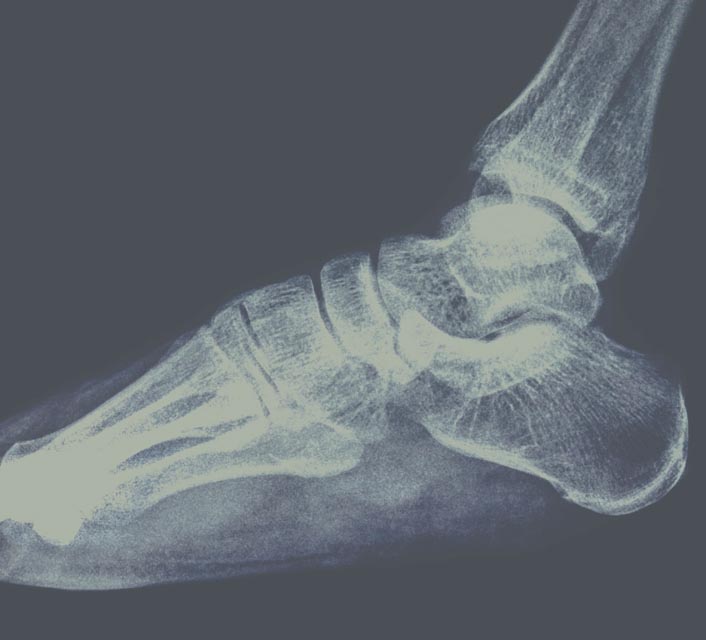

Onderzoek van uw voet middels moderne beeldvorming.